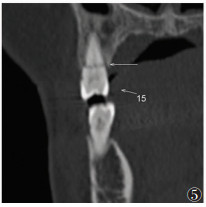

2 结果28例共49颗牙齿根折(图 1),其中单颗牙根折18例(64.3%),多颗牙根折10例(35.7%);中切牙根折39颗(79.6%),侧切牙根折10颗(20.4%);8例合并冠折;9例合并邻近牙槽突骨折;10例合并邻牙损伤,其中6例为牙齿缺如,4例为冠折(图 2,3)。49颗根折牙齿中,骨折线位于根颈1/3处12颗(24.5%),根中1/3处6颗(12.2%),根尖1/3处31颗(63.3%),以根尖1/3处最常见(图 4,5)。

| 图 5 男,31岁,15牙根中1/3处根折(箭头) |